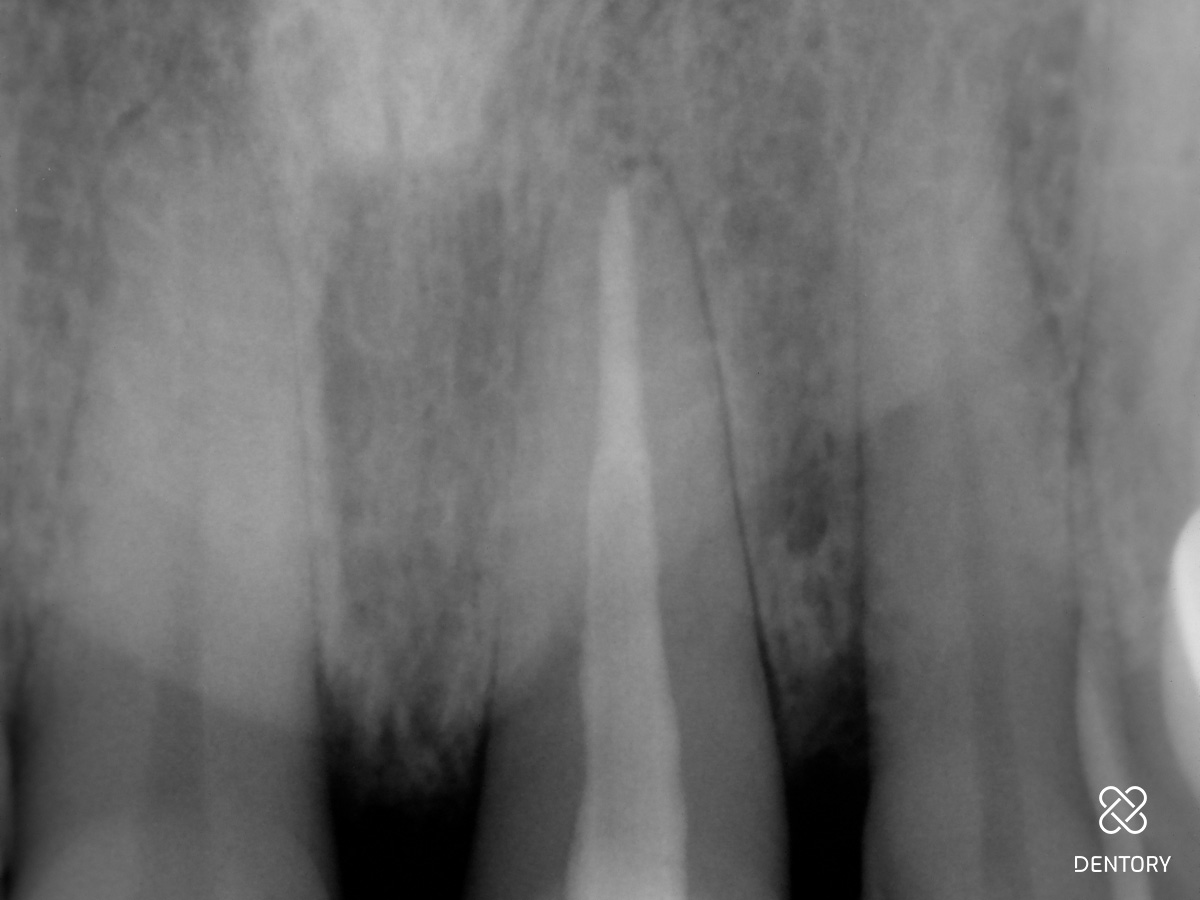

Abbildung 1

Ausgangssituation.